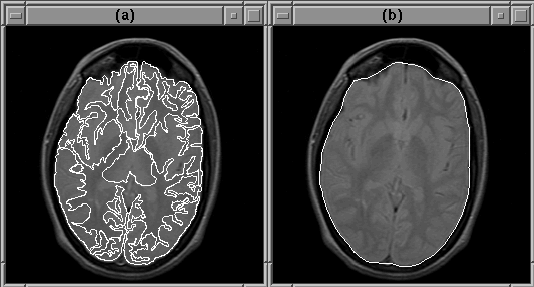

The intracranial boundary defined by the final brain mask of Data Set 1 is overlaid on the PD-weighted MR volume in Figure 8.17. The mask outlines the brain remarkably well in all slices. Figure 8.18 shows slice 13 at a higher resolution. Notice that the final mask covers the entire brain, whereas the initial mask lies inside the brain.

Figure 8.17: The final brain mask for MRI Data Set 1 overlaid on the PD-weighted scan.

Figure 8.18: A closeup of slice 13 of MRI Data Set 1. The Generate Final Brain Mask process enlarges the initial brain mask, (a), to cover the entire brain, (b).

Only slight errors occur in the first slice and some slices containing the eyes. In these slices, the brain mask excludes some very low intensity brain tissue. The errors are understandable since these low intensity tissues appear very similare to the intracranial cavity tissues.